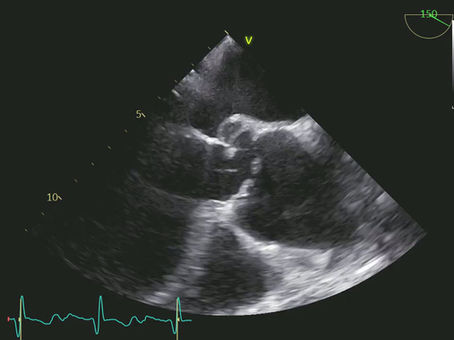

When a Urinary Tract Infection Does Not Explain Bacteremia. A Case Report of Sepsis, Klebsiella pneumoniae, and Missed Infective Endocarditis

Introduction Fever and bacteremia in older patients with an indwelling urinary catheter are frequently interpreted as urosepsis. In most cases this assumption is correct, but it may also lead to diagnostic anchoring. This case report illustrates how a rare but life-threatening cause of bacteremia was only uncovered after the clinical course failed to follow the expected trajectory. Patient Presentation and Admission A man in his seventies was admitted with fever, acute confus